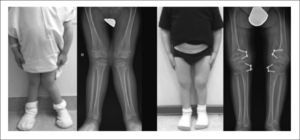

- Deformidades óseas en brazos, piernas, tórax o columna vertebral.

El diagnóstico se basa en la observación clínica, estudios radiológicos y, en la mayoría de los casos, pruebas genéticas que permiten confirmar la mutación responsable. En algunos casos graves, la displasia puede detectarse durante el embarazo mediante ultrasonido o pruebas genéticas prenatales.

- Cirugías ortopédicas para corregir deformidades o alinear huesos.